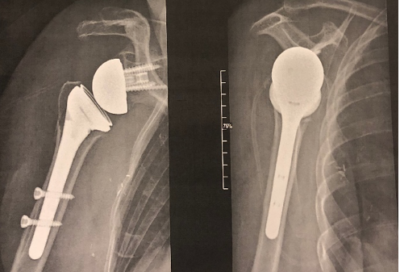

La prothèse inversée d’épaule

Qu’est-ce qu’une prothèse inversée d’épaule ?

Une prothèse d’épaule imite l’anatomie normale de l’épaule en reproduisant ses structures à l’aide d’une cupule fixée à l’omoplate qui imite la glène et d’une boule en métal qui imite la tête de l’humérus. Dans une prothèse inversée d’épaule, c’est la boule qui est fixée à l’omoplate et la cupule à l’humérus.

Face / Profil

Vous serez revu(e) en consultation de contrôle dans le mois qui suit l’intervention. Plusieurs radiographies de contrôle seront à réaliser au cours du suivi.